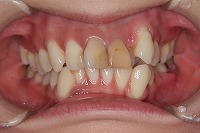

正面

前歯が出ていて歯並びが悪い事を主訴に来院された、26歳1か月の女性です。診断「歯と歯槽基底の大きさの不調和による叢生」上顎は右側第1小臼歯と左側の犬歯、下顎は抜歯をせず治療を行いました。